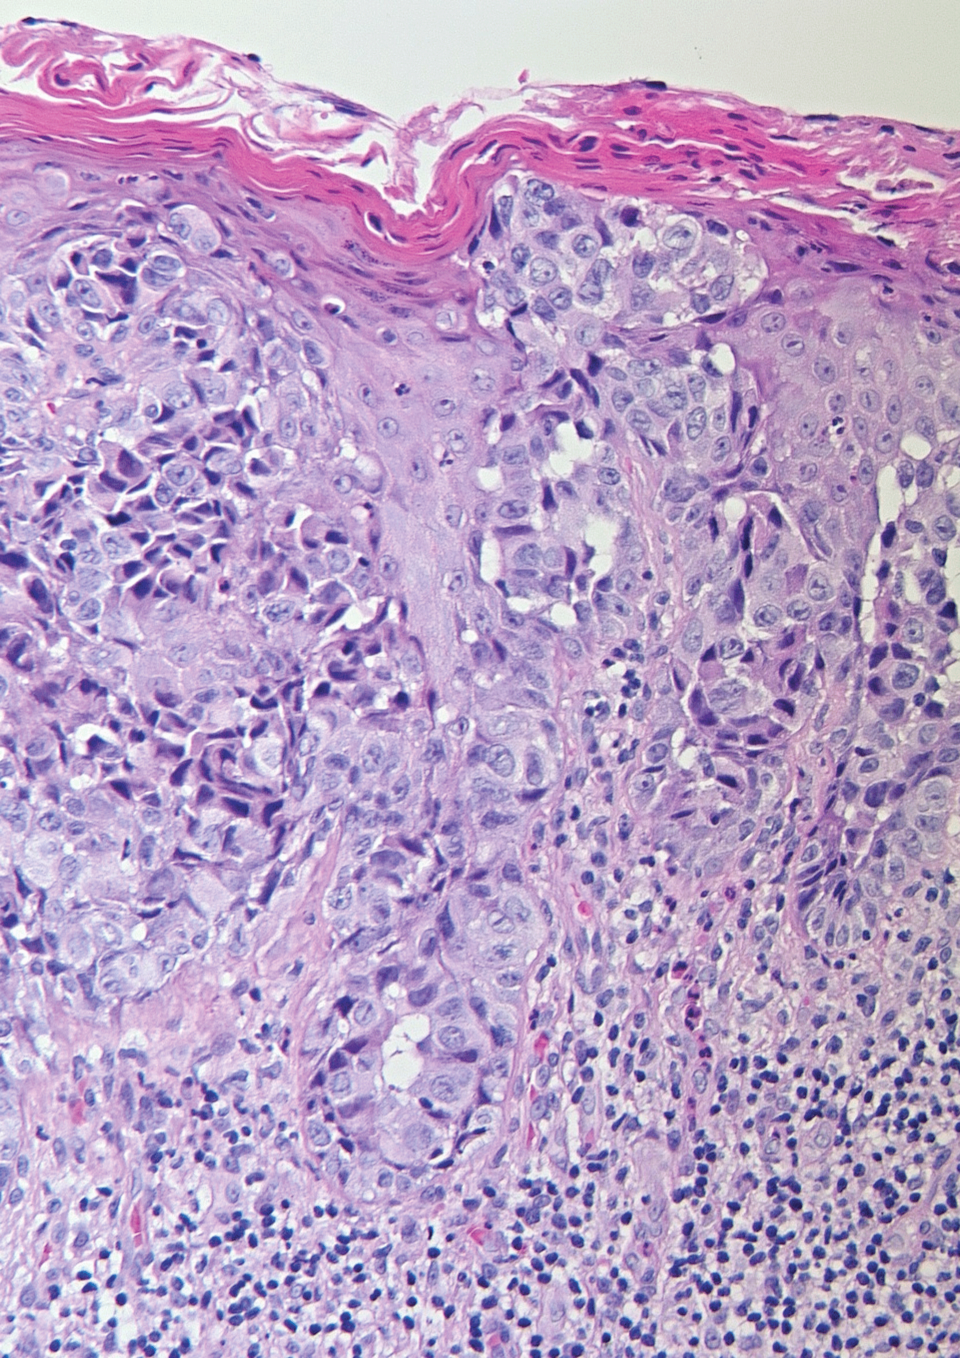

Große Krebszellen mit atypischen Kernen ziehen sich durchs gesamte Epithel. Große Krebszellen mit atypischen Kernen ziehen sich durchs gesamte Epithel. © Sorhage B. Wehrmed Monatsschr 2019; 63: 313-316 © Beta Verlag & Marketinggesellschaft mbH, Bonn